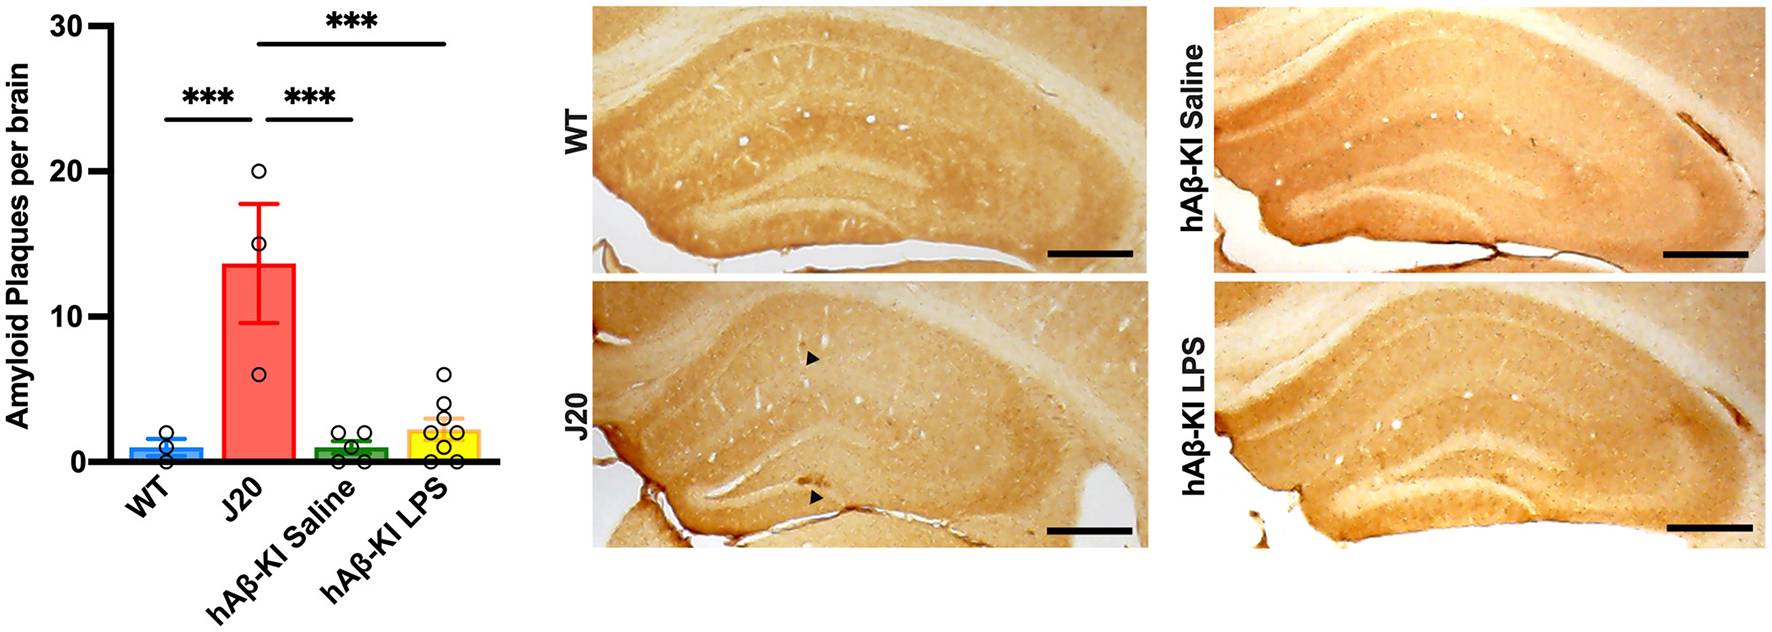

hAβ-KI mice do not show Aβ plaque pathology at 24 weeks

An important, yet highly debated feature of human AD is the accumulation of the protein Aβ, resulting in plaque formation throughout the brain. In the current study, we used the human-specific antibody 6E10 to measure Aβ deposition in the hippocampus. Quantification of 6E10 immunoreactivity revealed a significant increase in total Aβ plaques between groups [One-way ANOVA F(3, 15) = 13.68, p < 0.001; Figure 5] and Bonferroni post-hoc analysis indicated that exclusively J20 mice had significantly increased Aβ deposition when compared to every other group (p < 0.001). Notably, despite finding significant memory deficits and spine loss in hAβ-KI mice at 24 weeks of age, there was little to no Aβ deposition seen at this timepoint.

Figure 5. J20 mice display plaque deposition in the hippocampus. 6E10 immunohistochemistry illustrated increased Aβ deposition in J20 mice when compared to any other group. Scale bar 250 μm. All values represent the mean ± standard error of the mean (SEM). WT n = 3, J20 n = 3, hAβ-KI saline n = 5, hAβ-KI LPS n = 8. ***p < 0.001.